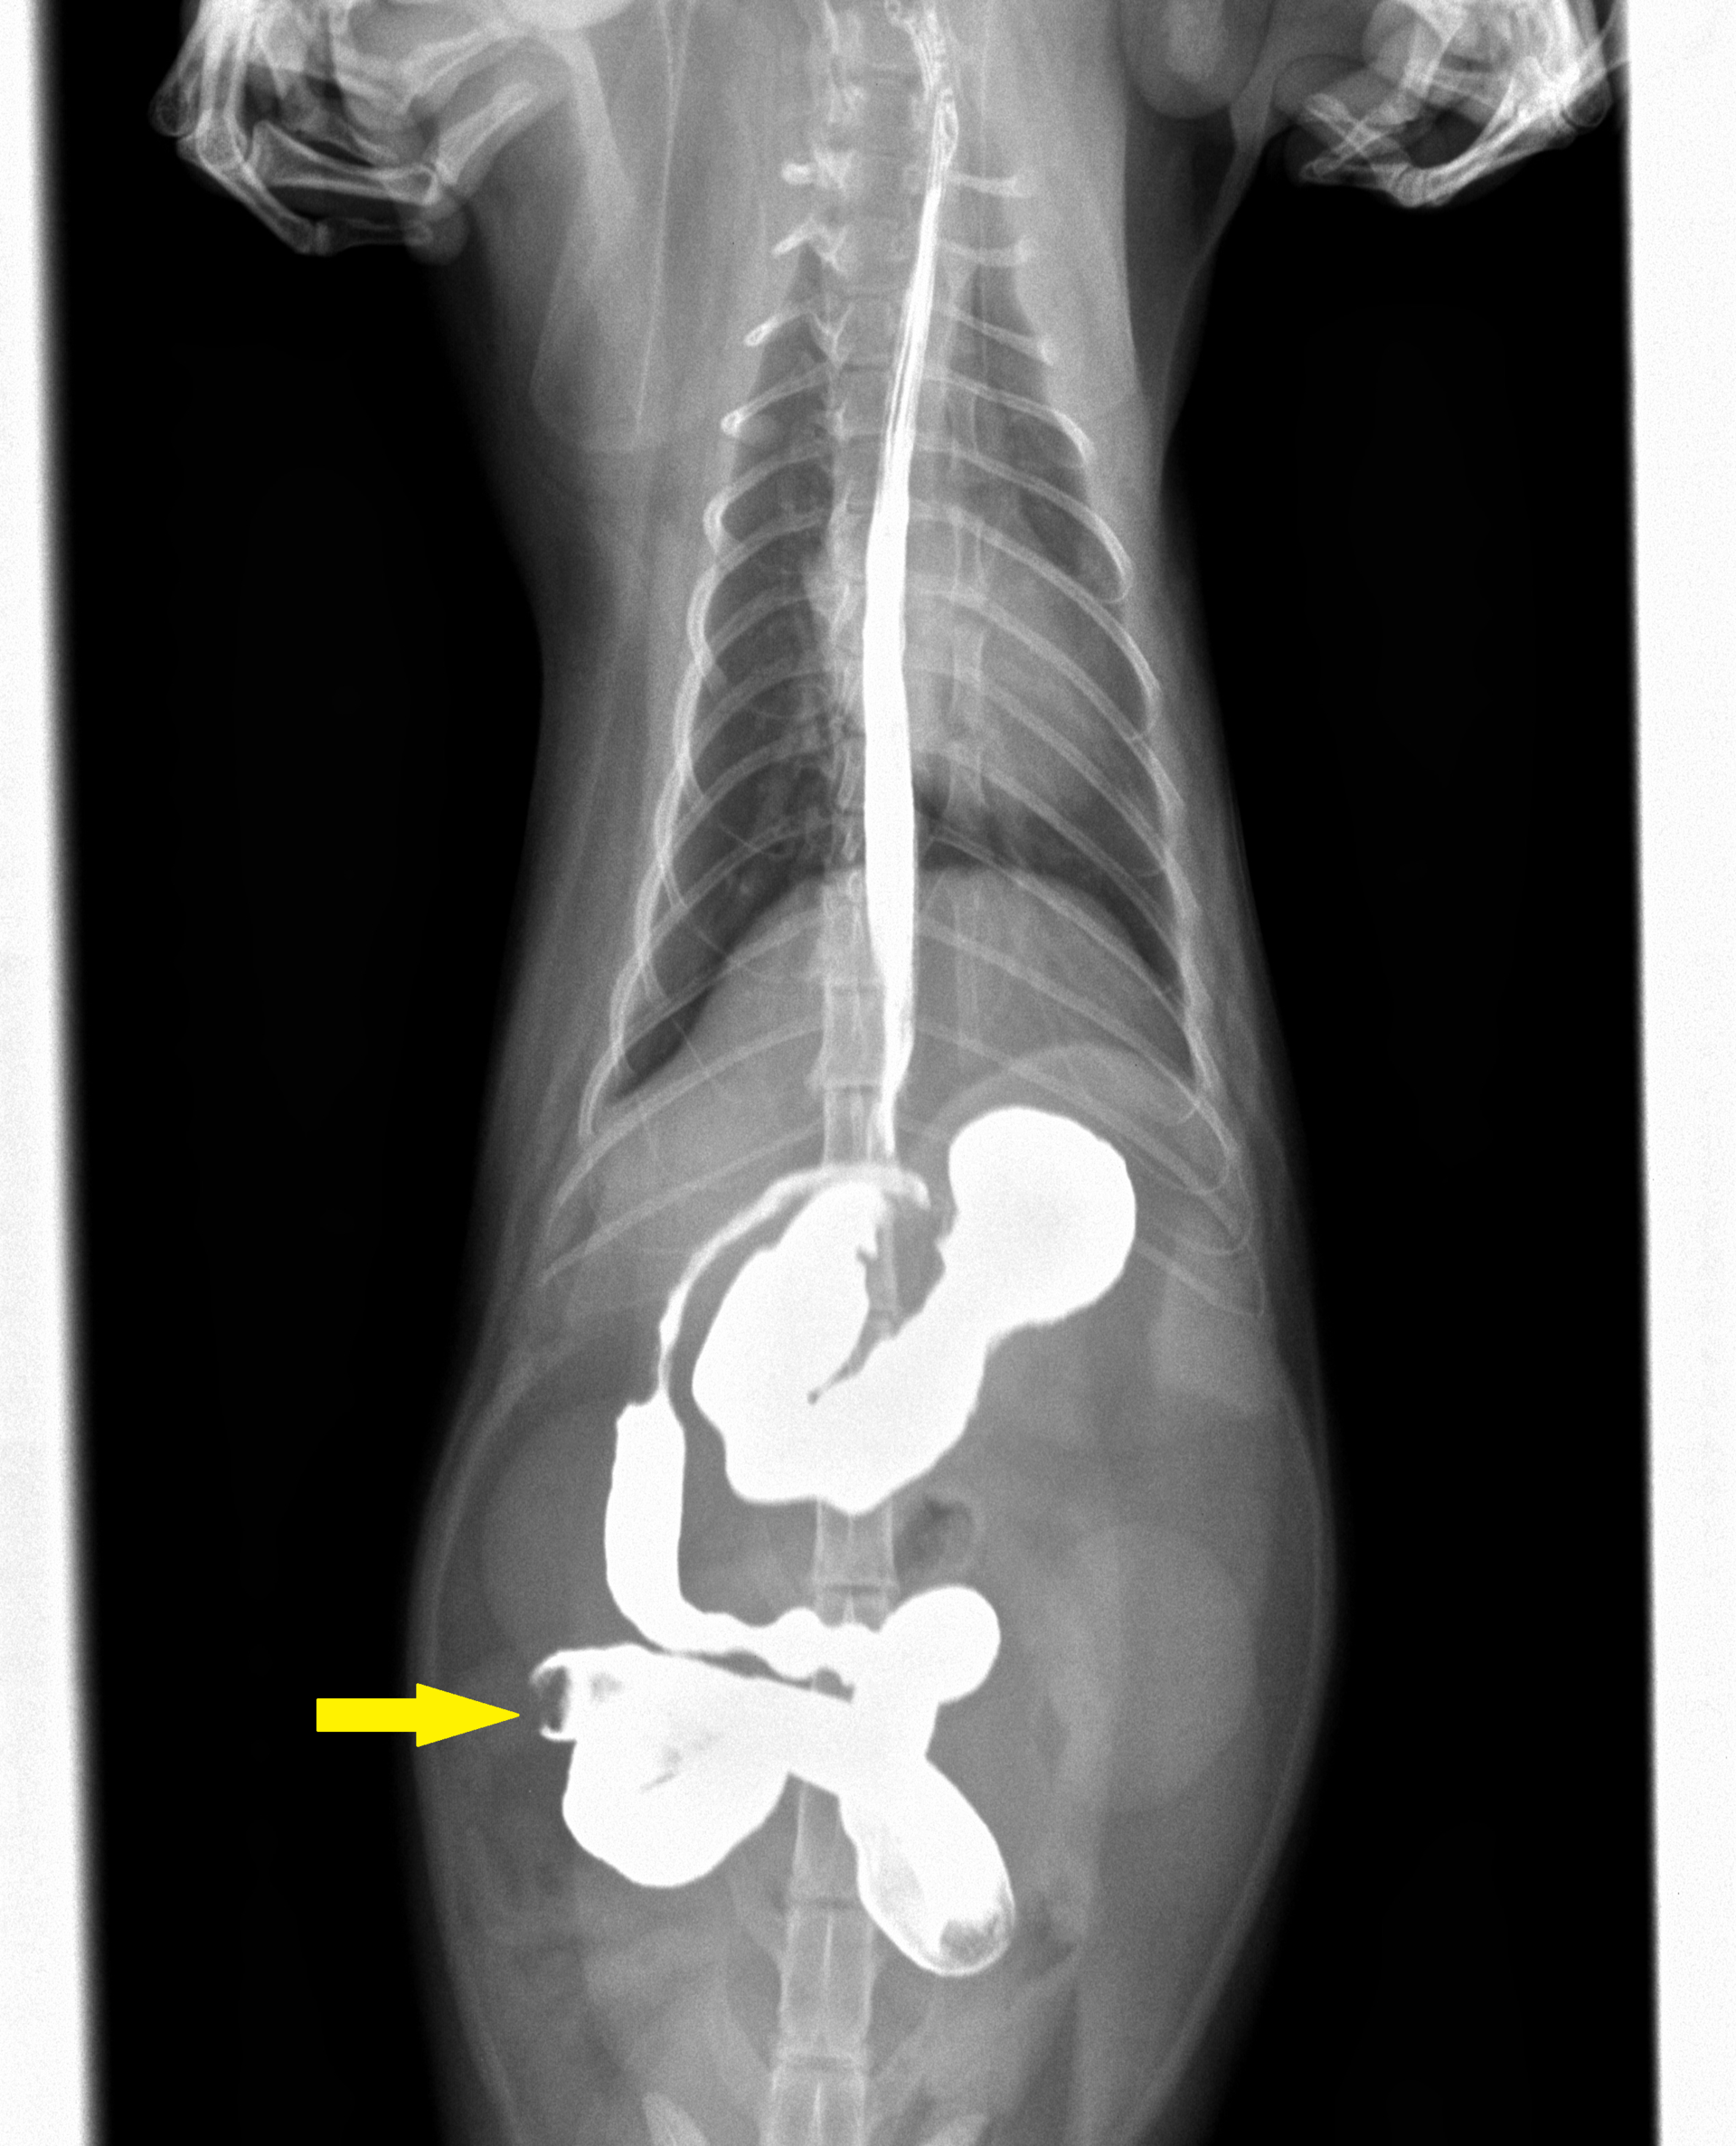

診察初日は点滴をし、その当日の絶食絶水を指示し、その日は自宅で様子を見ていただきました。しかしその次の日、嘔吐は治まらず吐き続けているということで来られました。そこで、異物がないかバリウム検査を行いました。その結果が下の写真です。

投与60分後

バリウムを投与後、15分も60分も同じところ(矢印)でストップして全く流れていないことがわかります。異物による通過障害が考えられたので、当日緊急手術となりました。その様子が下の写真です。